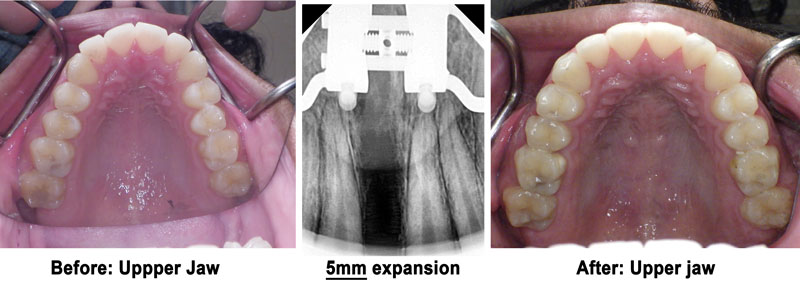

However, in extremely narrow cases with a deficiency of more than 5 mm, "like Fig. 1” or in older patients, the traditional RPE might not work for the upper jaw, and a more aggressive approach might be needed to open the mid-palatal suture.

Notice the above sequence of changes in her upper jaw width. The X-rays below also show her expansion and suture opening after stage one and after stage two.

This patient has been on allergy medications for years to improve their breathing. However, after watching Dr. Kanaan with Debra Duncan talking about MARPE and its benefits, he decided to undergo the MARPE procedure. Dr. Kanaan placed the MARPE with longer screws to maximize its force. His case was a complete success with over 5 mm of expansion in his basal nose level. Patient was pleased with his MARPE treatment in Houston.

Notice the excellent expansion on the X-ray and how it was filled with bone.